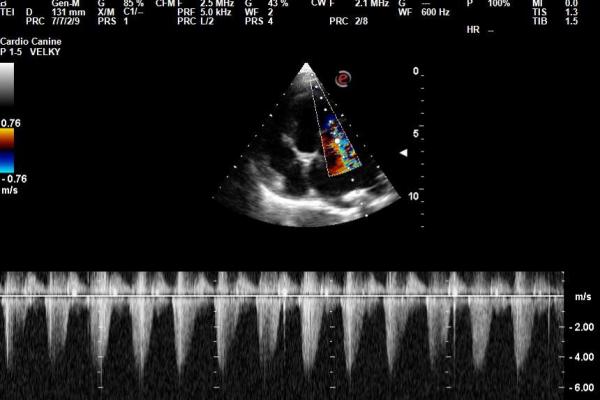

Vyšetření nitroočního tlaku kočky tonometrem iCare Tonovet Pro | Veterinární klinika Medipet Zlín